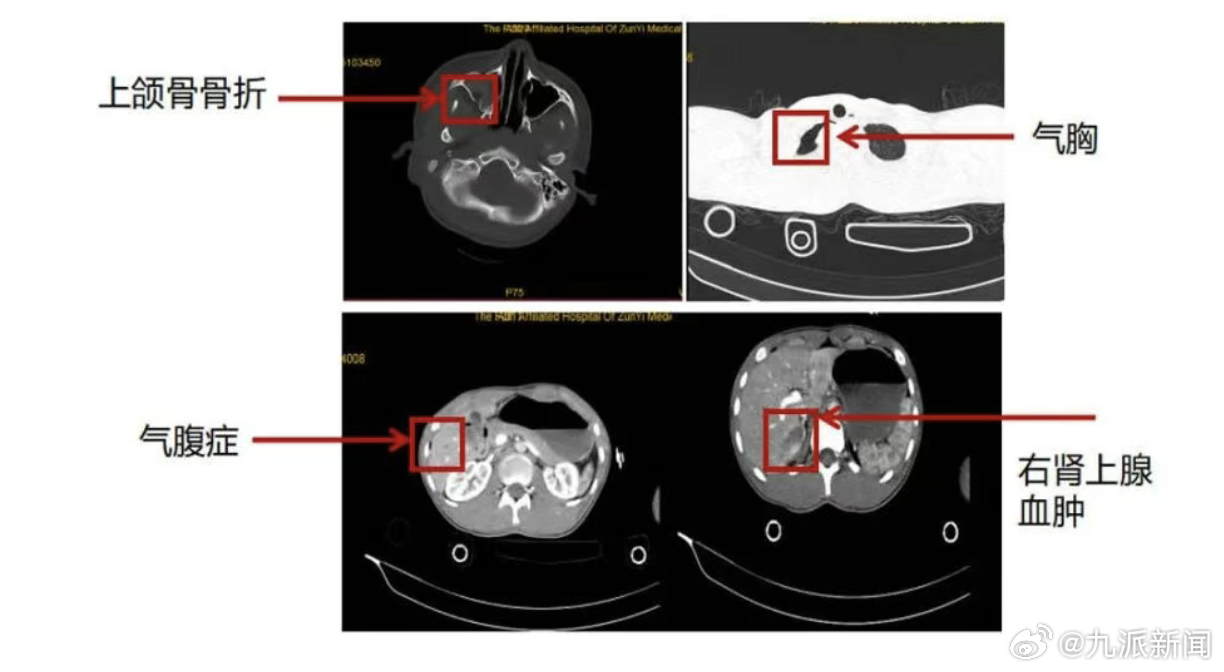

【#男子5楼坠落严重休克奇迹生还#】12月15日,从遵义医科大学第五附属医院获悉:近日,广东珠海斗门一名男子因意外从5楼坠落,被紧急送往遵义五院。救护车抵达时,急诊医生发现伤者浑身是血,多处骨折,右腕及双小腿畸形,呼吸微弱、皮肤苍白,送医时已严重休克。时间紧迫,鉴于伤者高空坠落、多处重伤,医院立即启动创伤中心最高级别响应。专家结合影像科医师初步研判结果指出:“下唇贯通伤、下颌部裂伤,需即刻清创缝合;肠系膜破裂,需紧急行腹腔探查术;双侧胫腓骨、右距骨、右踝关节开放性骨折,优先行损伤控制手术。”多学科专家团队依据实时影像数据,迅速完成伤情研判,确定核心抢救方案:立即实施损伤控制手术,先止血救命,待患者生命体征平稳后,再行分期手术治疗。手术室内,血液回输机高速运转,急救药品整齐排列,各类手术器械摆放有序。有人专注处理腹部止血,精准控制出血点;有人迅速开展骨折临时固定,避免二次损伤;有人紧盯监护仪,全力维持患者生命体征……整套操作行云流水。耗时约2小时,首次损伤控制手术顺利完成,患者被平稳送入重症监护室。此时患者生命体征已趋于平稳,为后续治疗奠定了坚实基础。待病情进一步稳定后,骨一科、骨二科专家先后为其开展四肢骨折修复手术及脊柱手术,康复治疗也同步介入,形成了“抢救-治疗-康复”的完整诊疗闭环。